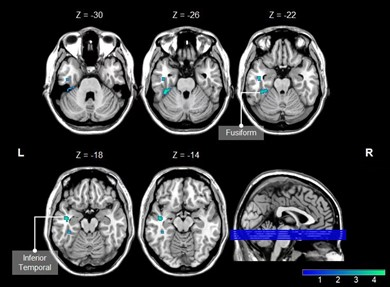

There were statistical differences in MoCA score, correct number of free recall in CVLT1 experiment, TMT-A, TMT-B and DSST between the two groups (p < 0.05) (Table 1). The CBF value was significantly reduced in brain regions of the left Fusiform (Fusiform-L) and the left Temporal Inferior (Temporal Inf – L) in the HD group compared with the HC group. The voxels, MNI coordinates, and peak intensity for these regions are shown in Table 2. Mean CBF in Fusiform -L was positively correlated with cognition (r = 0. 455, p = 0.012), and mean CBF in Temporal Inf - L was negatively correlated with TMT-A (r = -0.389, p = 0.030) (Figure 2).

Figure 2. a. the correlation between mean CBF of Fusiform -L and recognition; b. the correlation between mean CBF of Temporal Inf - L and TMT-A.